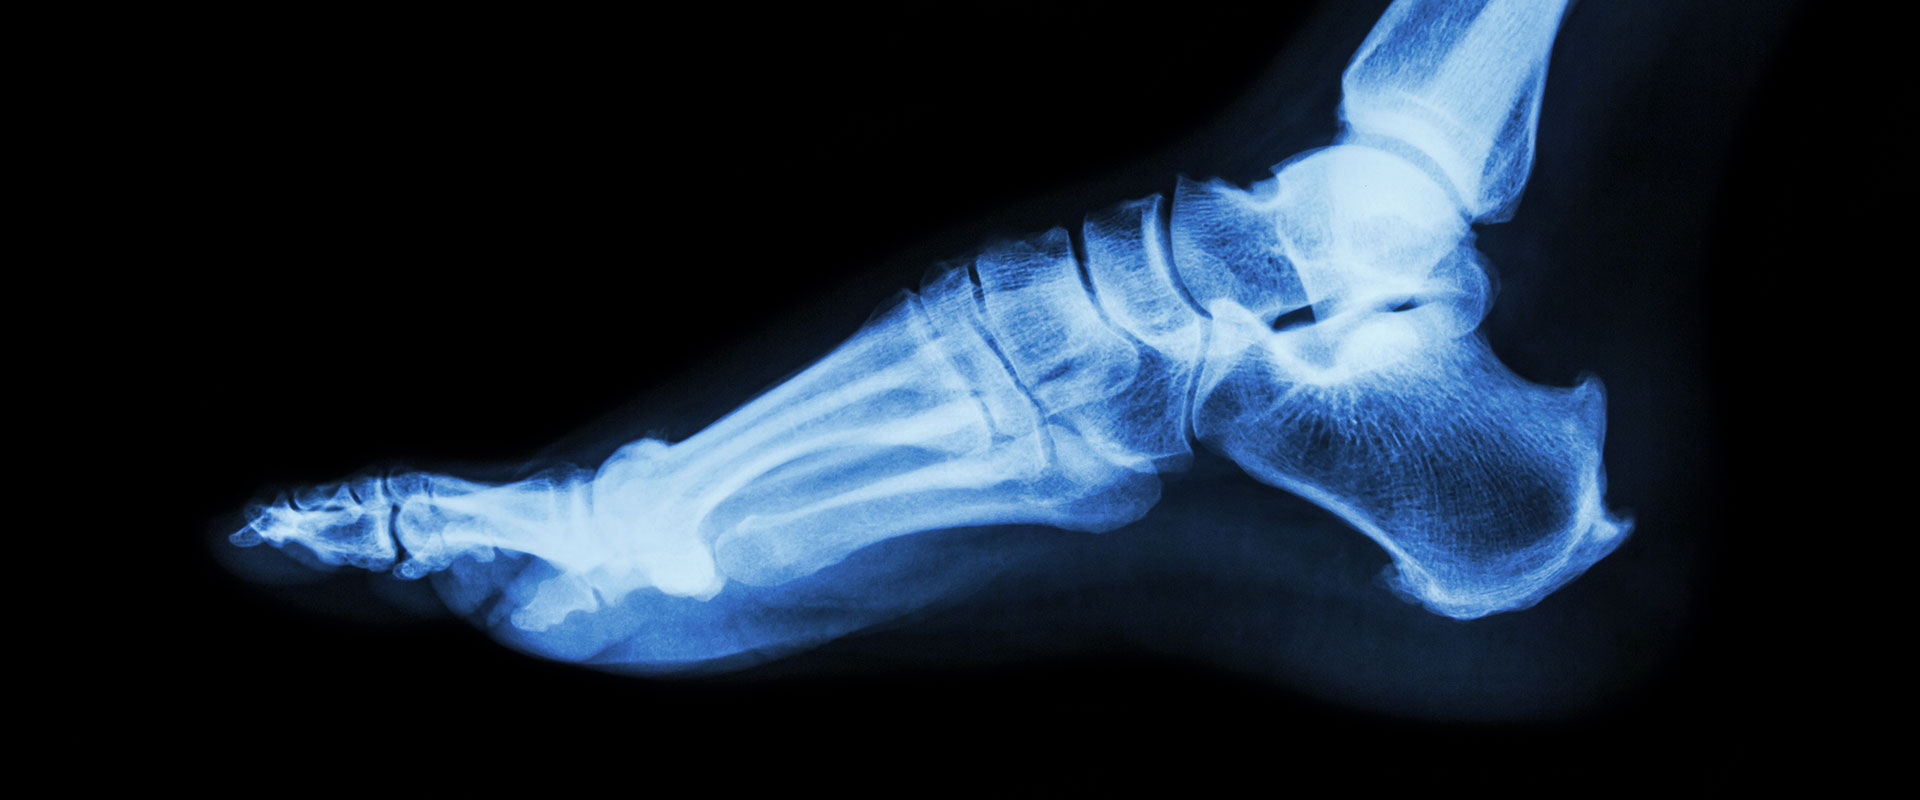

Röntgen ist eine medizinische Untersuchungsmethode, bei der Röntgenstrahlen verwendet werden, um Bilder des Inneren des Körpers zu erzeugen. Diese Strahlen sind eine Form von elektromagnetischer Strahlung und können durch Gewebe hindurchdringen. Beim Durchgang durch den Körper werden die Strahlen von verschiedenen Geweben unterschiedlich stark absorbiert, was zu einem Kontrast auf den erzeugten Bildern führt. Röntgenbilder können verwendet werden, um Knochenbrüche, Tumore, Infektionen und andere Erkrankungen zu diagnostizieren.